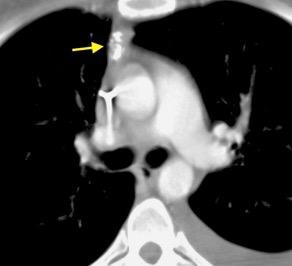

99.GANGLIOS CON HIPERCAPTACIÓN TRAS

CONTRASTE